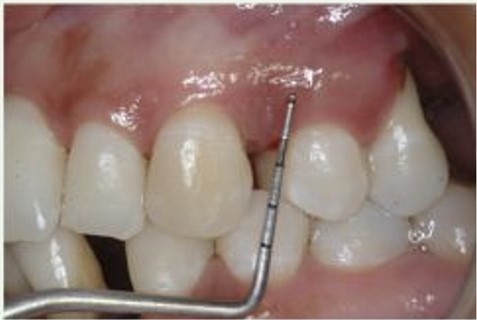

Profundidade de Sondagem aumentada

Exame Radiográfico

O exame Radiográfico é muito importante, deve ser observado o volume e a posição da crista óssea para que se tenha uma melhor condição de previsibilidades, viabilidade e escolha da técnica a ser utilizada. (RX Periapical e Interproximal)